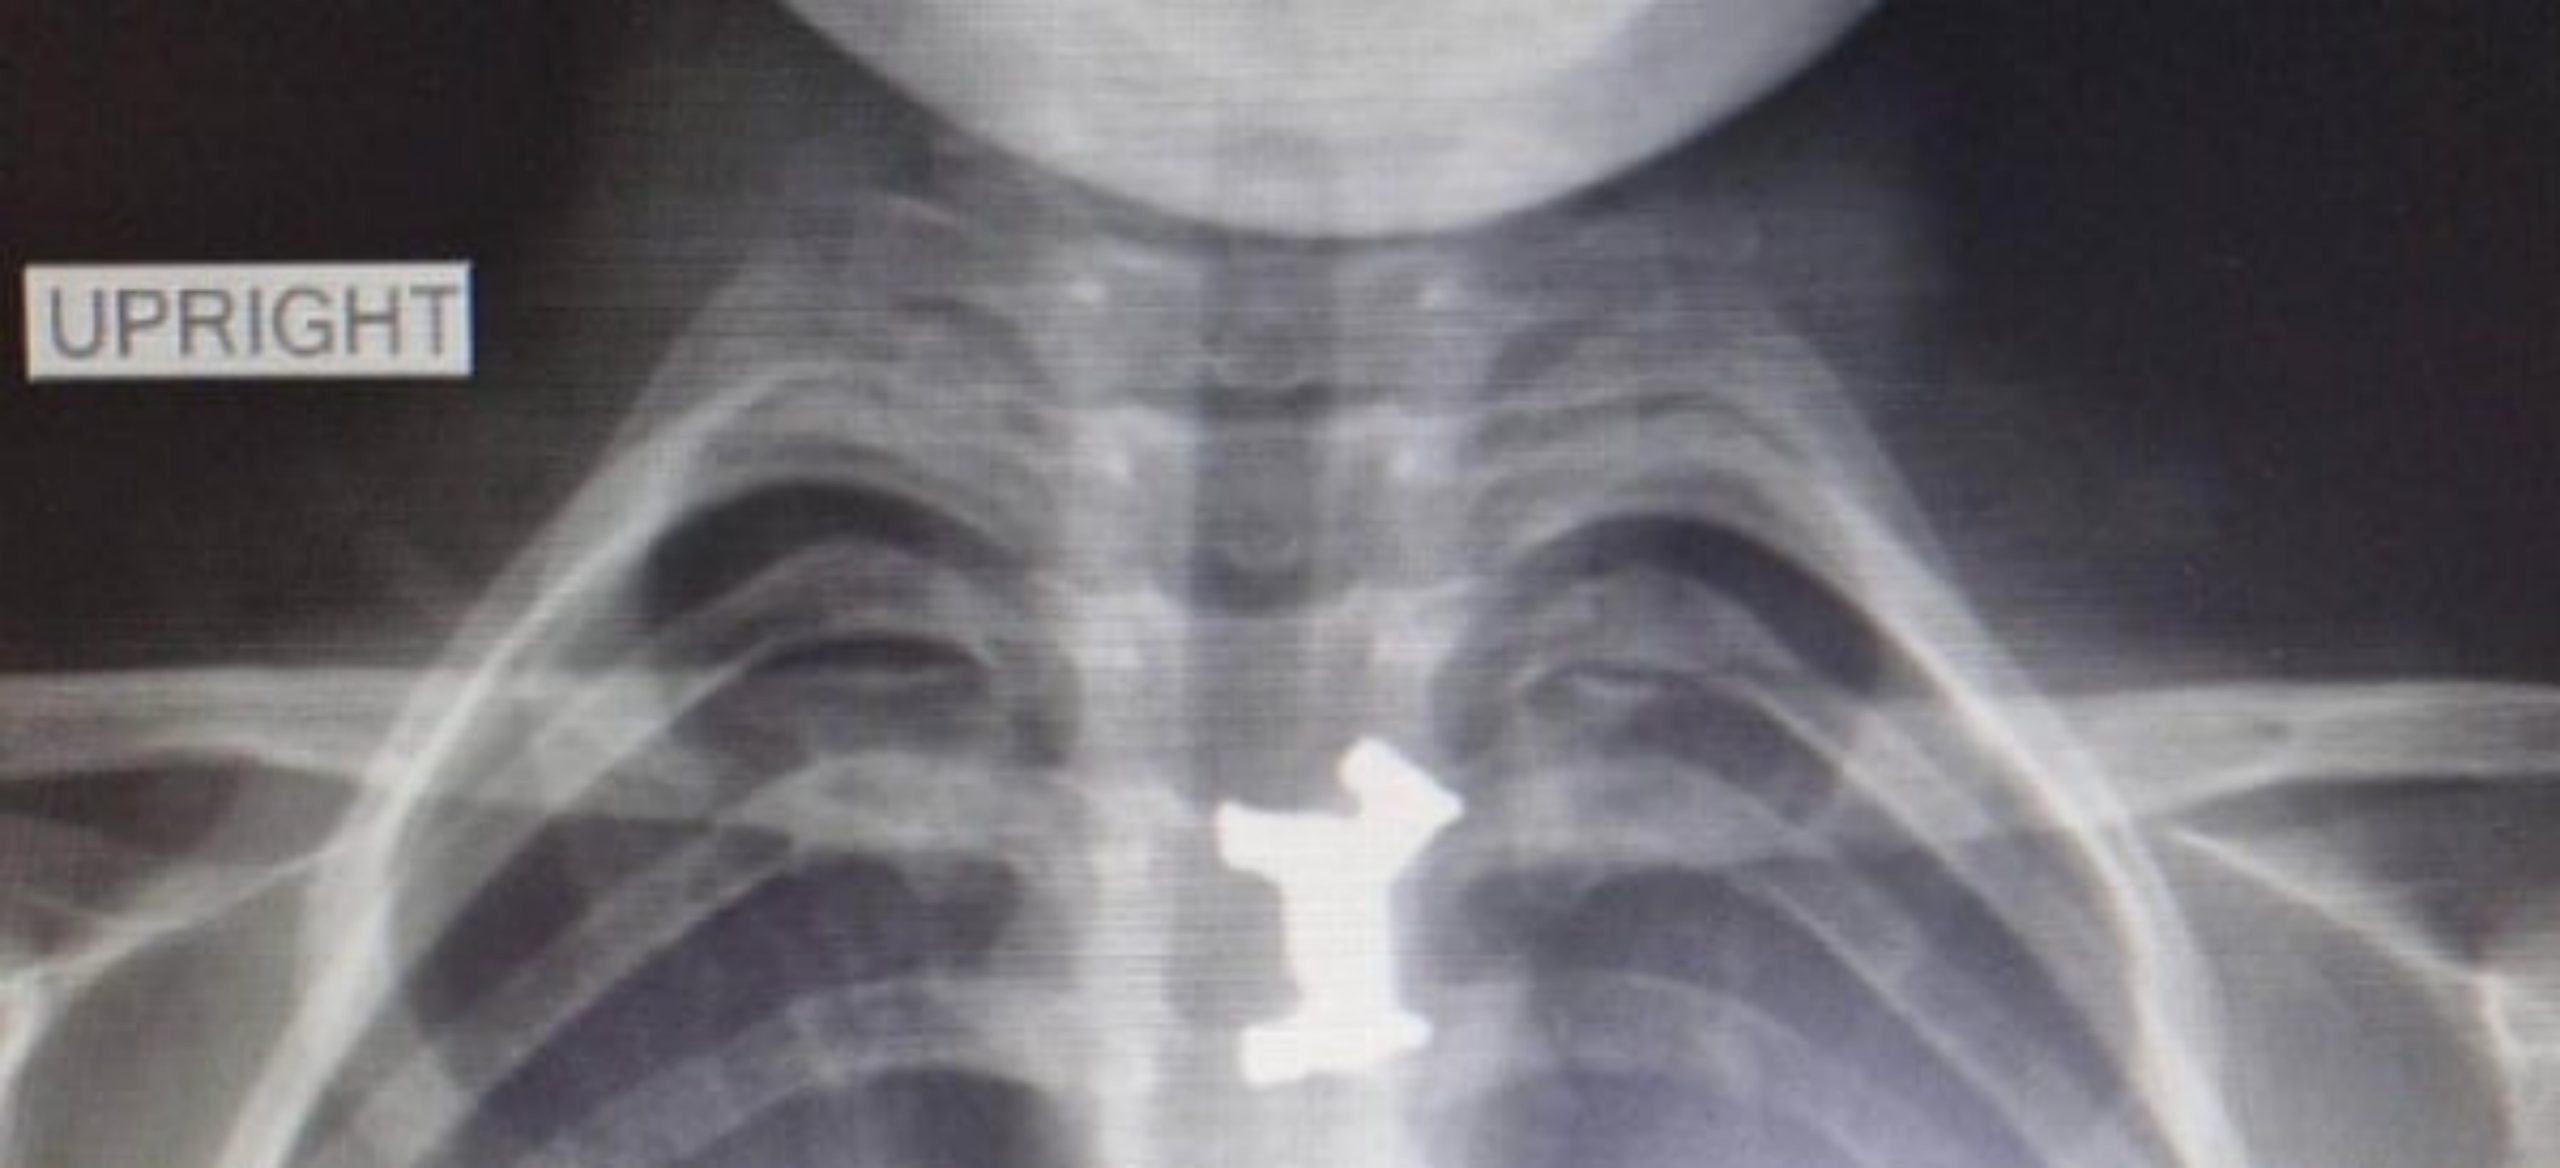

Αγωνία στη Θεσσαλονίκη – Αγοράκι 4,5 ετών κατάπιε μεταλλικό πιόνι. Το έσωσαν οι γιατροί στο Ιπποκράτειο

Στα Επείγοντα της Παιδιατρικής Κλινικής του Ιπποκράτειου νοσοκομείου, στη Θεσσαλονίκη, μετέβη στις 4:00 η ώρα τα…